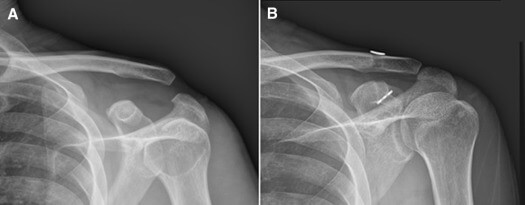

în funcţie de gradul de ruptură şi de deplasare a claviculei faţă de acromion disjuncţiile sunt clasificate în 6 tipuri. Metoda care mi s a părut cea mai eficientă şi care permite refacerea structurilor anatomice constă în coborârea şi menţinerea claviculei în poziţie normală folosind un dispozitiv special numit tight rope un ansamblu de sfori foarte rezistente ce au la ambele capete nişte. Etiopatogenie disjunctia acromio claviculara este frecventa la adultul tanar preponderent de sex masculin mai frecvent in contextul traumatismelor sportive. Dar va sfatuiesc cu medicul curant legat de conduita postoperatorie.

Disjuncţia acromio claviculară apare ca urmare a unor traumatisme sportive rugby hockey fotbal judo ciclism călărie ski etc mecanismul fiind căderea directă pe umăr sau pe mâna întinsă. In urma unei accidentari datorata unei caderi pe umarul stang am fost diagnosticat cu disjunctie acromio claviculara clasificata de unii doctori ca fiind de gradul 1 2 iar de altii de aproape gradul 3. Aceste sfaturi depind de tehnica operatorie. Aţi suferit un accident.